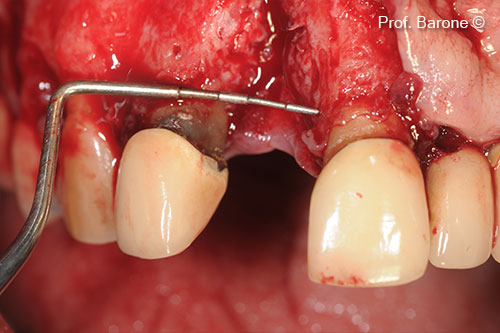

Residual Bone Defect, mesio-distal dimension

: Residual Bone Defect, vertical dimension